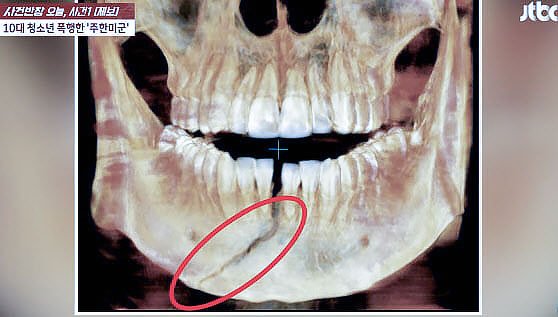

평택에서 30대 주한미군 부사관이 10대 청소년을 폭행해 턱뼈가 부러지는 사건이 발생했다.